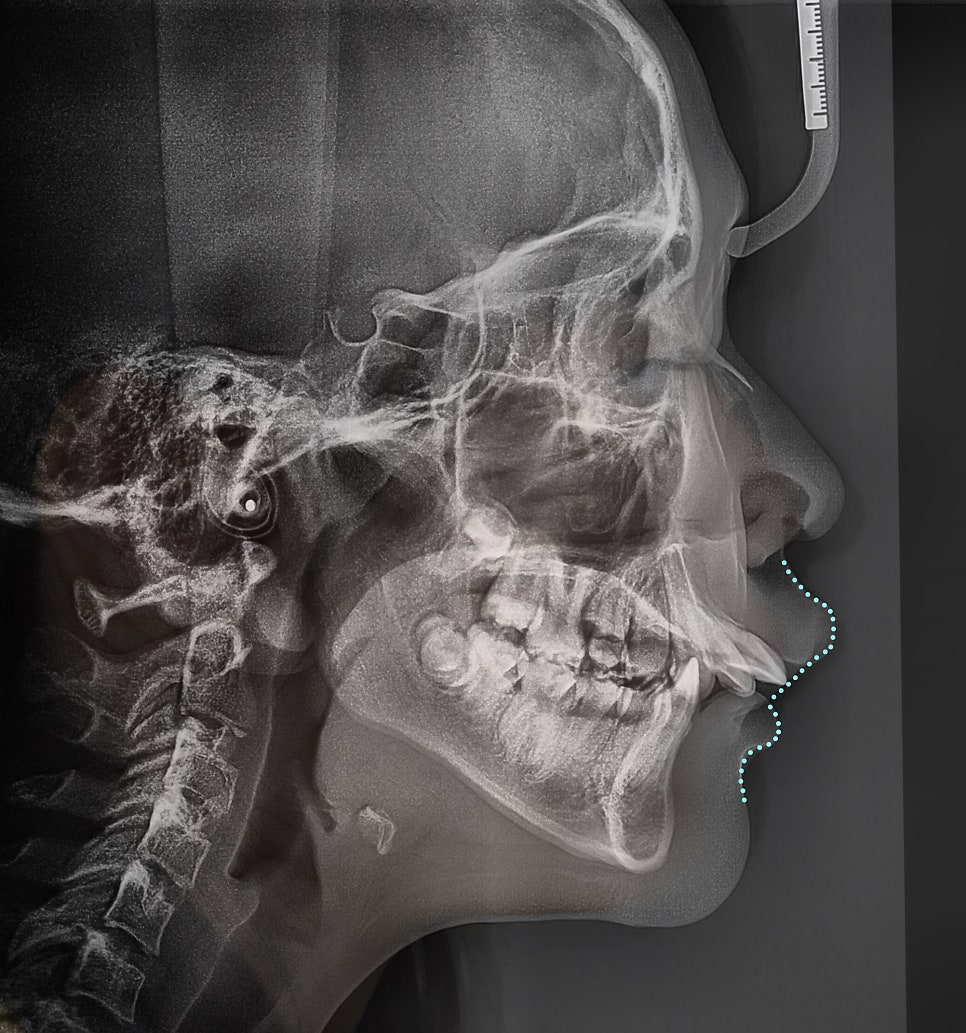

부정교합 2급 이라는 것은, 하악보다 상악이 더 전방에 위치되거나 또는 상악의 치아들이, 하악 치아들보다 더 앞쪽에 위치되어 있는것을 뜻하며

증세를 갖고 계셨던 분의 임상 증례를 보여드립니다. 교정 치료를 통해서 2급 부정교합이 개선 되었으며 치료를 끝으로, 턱 끝에 보형물